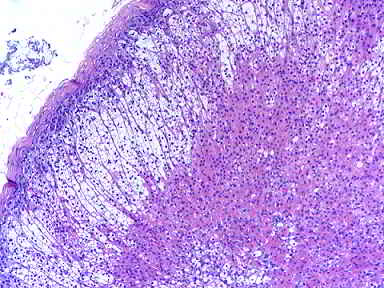

Figura 2 y 3: Cortes Histológicos de H y E. Muestra tejido adrenal organizado detectado en el nódulo resecado del saco herniario.